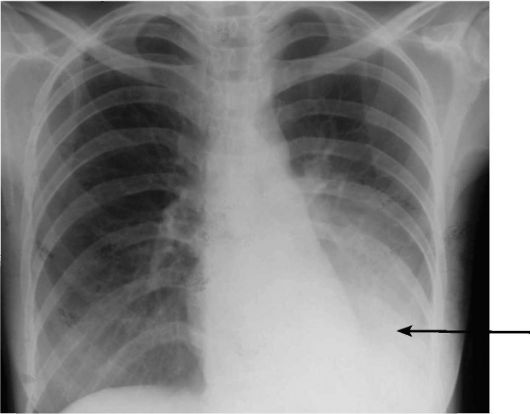

Если боль очень сильная, острая, колющая, отдаёт в руку, плечо, усиливается при дыхании и кашле – это пневмоторакс (скопление газов в плевре лёгких). Человеку хочется сидеть или занять полулежачее положение, появляются одышка и холодный пот, паника. Диагностируется рентгенографией и пункцией лёгких.

- Пневмоторакс – попадание воздуха в плевральную полость в результате проникающего ранения острым орудием или обломком ребра вследствие его перелома. Характер боли интенсивный, режущий либо колющий. Особенно больно становится, если принять лежачее положение, поэтому нужно сидеть на кровати, высоко подперев спину подушками.

- Инфаркт легкого – омертвение легочной ткани вследствие закупорки артерии, отвечающей за кровоснабжение органа. Помимо одышки и тахикардии патология может вызывать выделение крови при кашле.